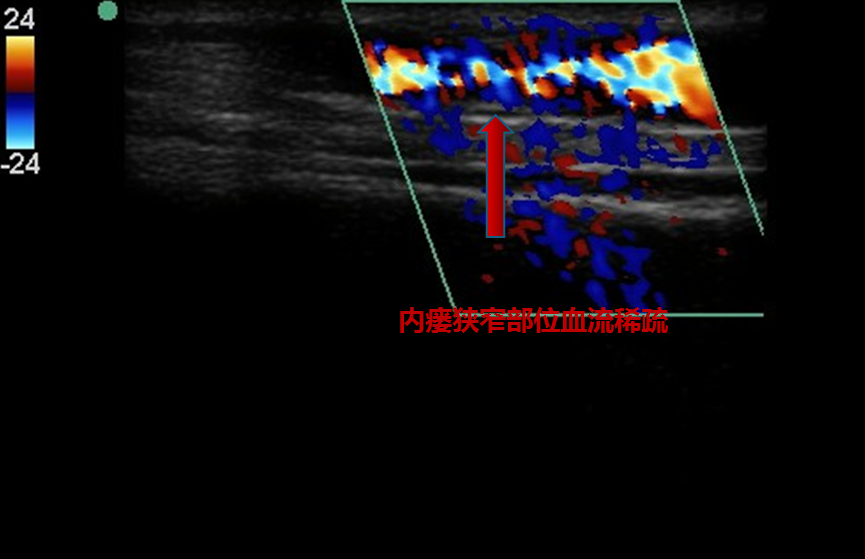

患者因自身血管条件差等因素造成内瘘狭窄

▲ 扩张前